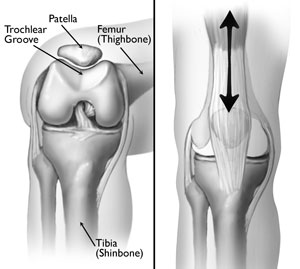

AnatomyYour knee is the largest joint in your body and one of the most complex. It is made up of the lower end of the femur (thighbone), the upper end of the tibia (shinbone), and the patella (kneecap).

Several structures in the knee joint make movement easier. For example, the patella rests in a groove on the top of the femur called the trochlea. When you bend or straighten your knee, the patella moves back and forth inside this trochlear groove.

Normal knee anatomy

(Left) The patella normally rests in a small groove at the end of the femur called the trochlear groove. (Right) As you bend and straighten your knee, the patella slides up and down within the groove.